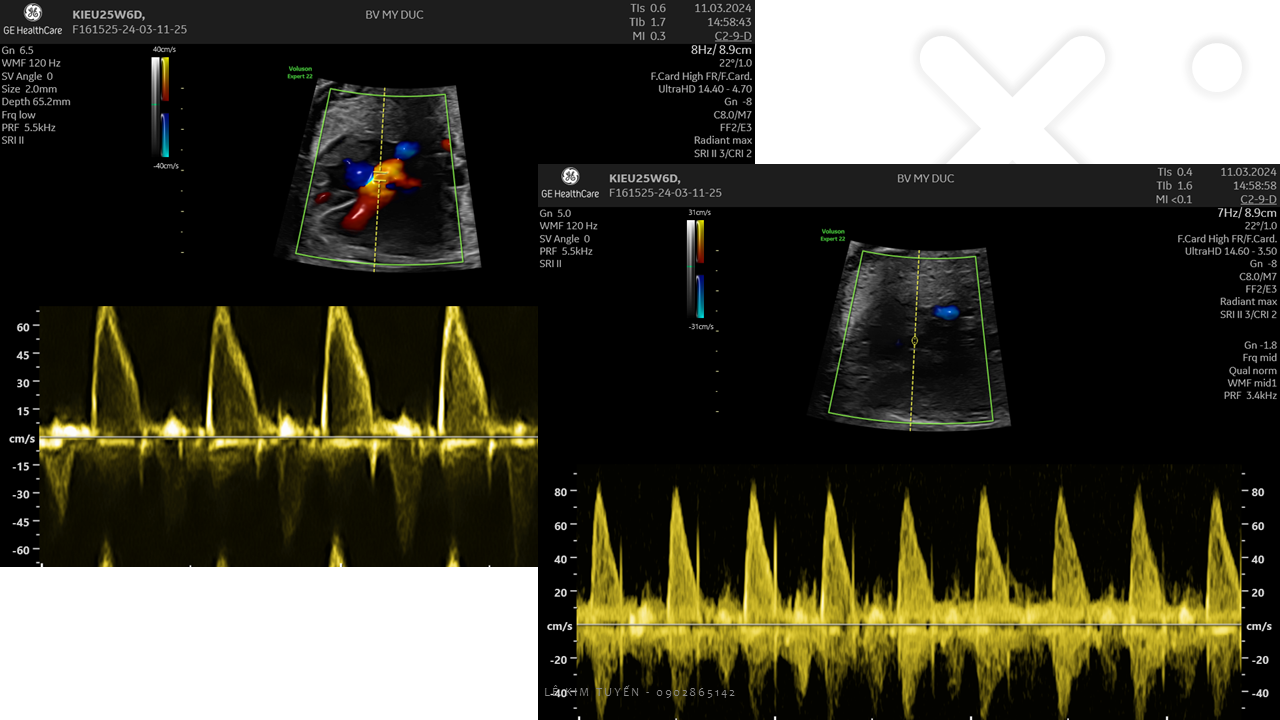

Siêu âm tim thai - Các kỹ thuật hiện đại

TS. BS. Lê Kim Tuyến

Bệnh viện Tim Tâm Đức